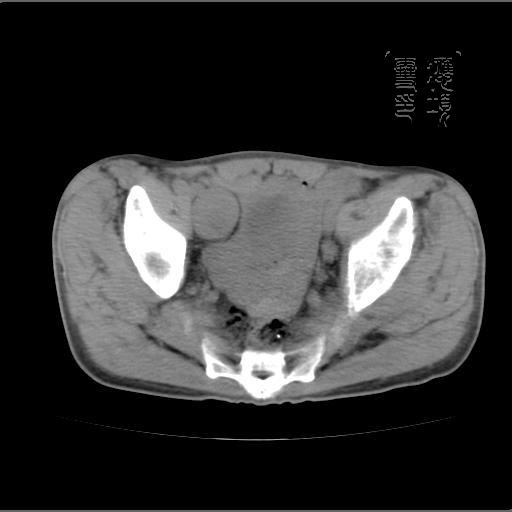

以下是引用余辉在2007-4-20 20:03:00的发言:[br]没头绪,猜一个吧,距离血管鞘近,就猜神经鞘瘤,中心部分变性囊变,另外请哪能位老师指点腹直肌后方及后外方强化物是何

以下是引用dyqct在2007-4-20 20:51:00的发言:[br]考虑:1、右侧膀胱外上方实性富血管性肿瘤(神经鞘膜瘤?纤维瘤?巨淋巴结增生症?)[br] 2、请标识需要解释的地方。

以下是引用aa13877358820在2007-4-21 7:01:00的发言:[br]隐睾?